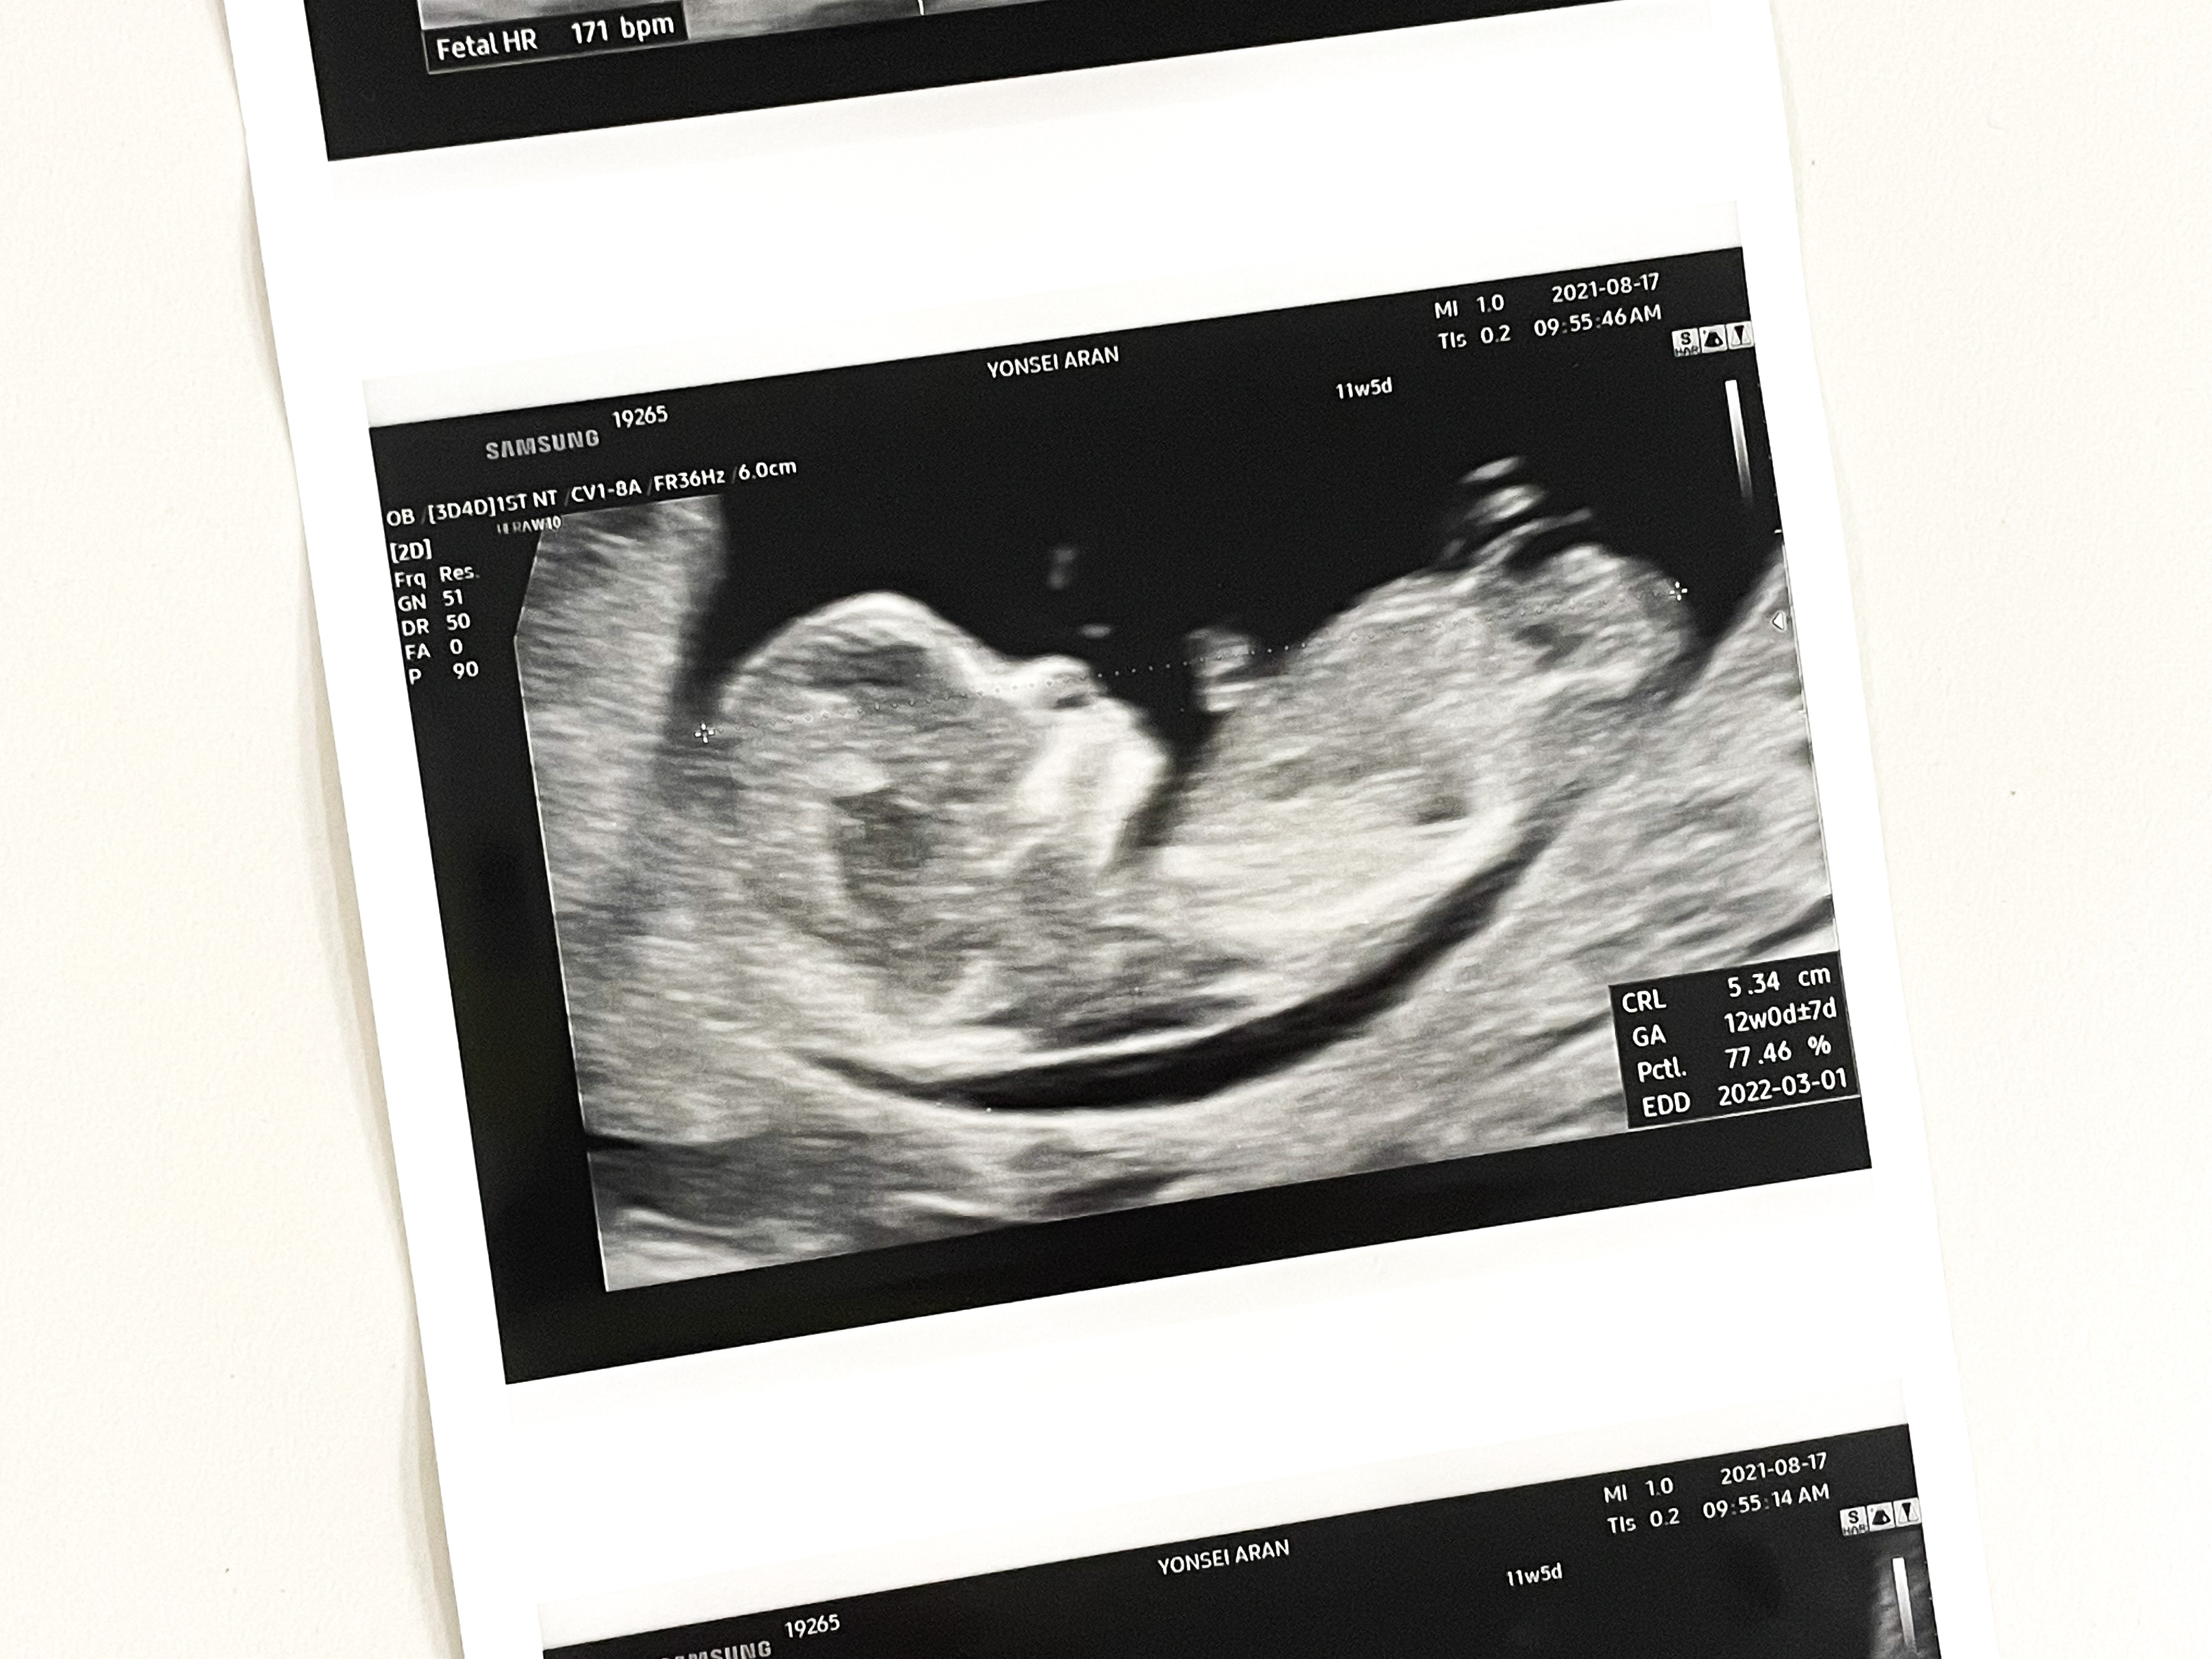

11주 5일

1차 기형아 검사를 받으러 갔다.

목투명대 검사

첫 검사는 정밀 초음파 검사실에서 이루어지는 목투명대 검사였다.

목투명대 길이 정상범위는 3mm 미만인데 1.05mm가 나왔다.

그리고 주수에 맞게 잘 크고 있었다.

비어있던 머리 공간도 어느새 나비가 자리잡고 있었다.

입체 초음파도 찍어주셨다.